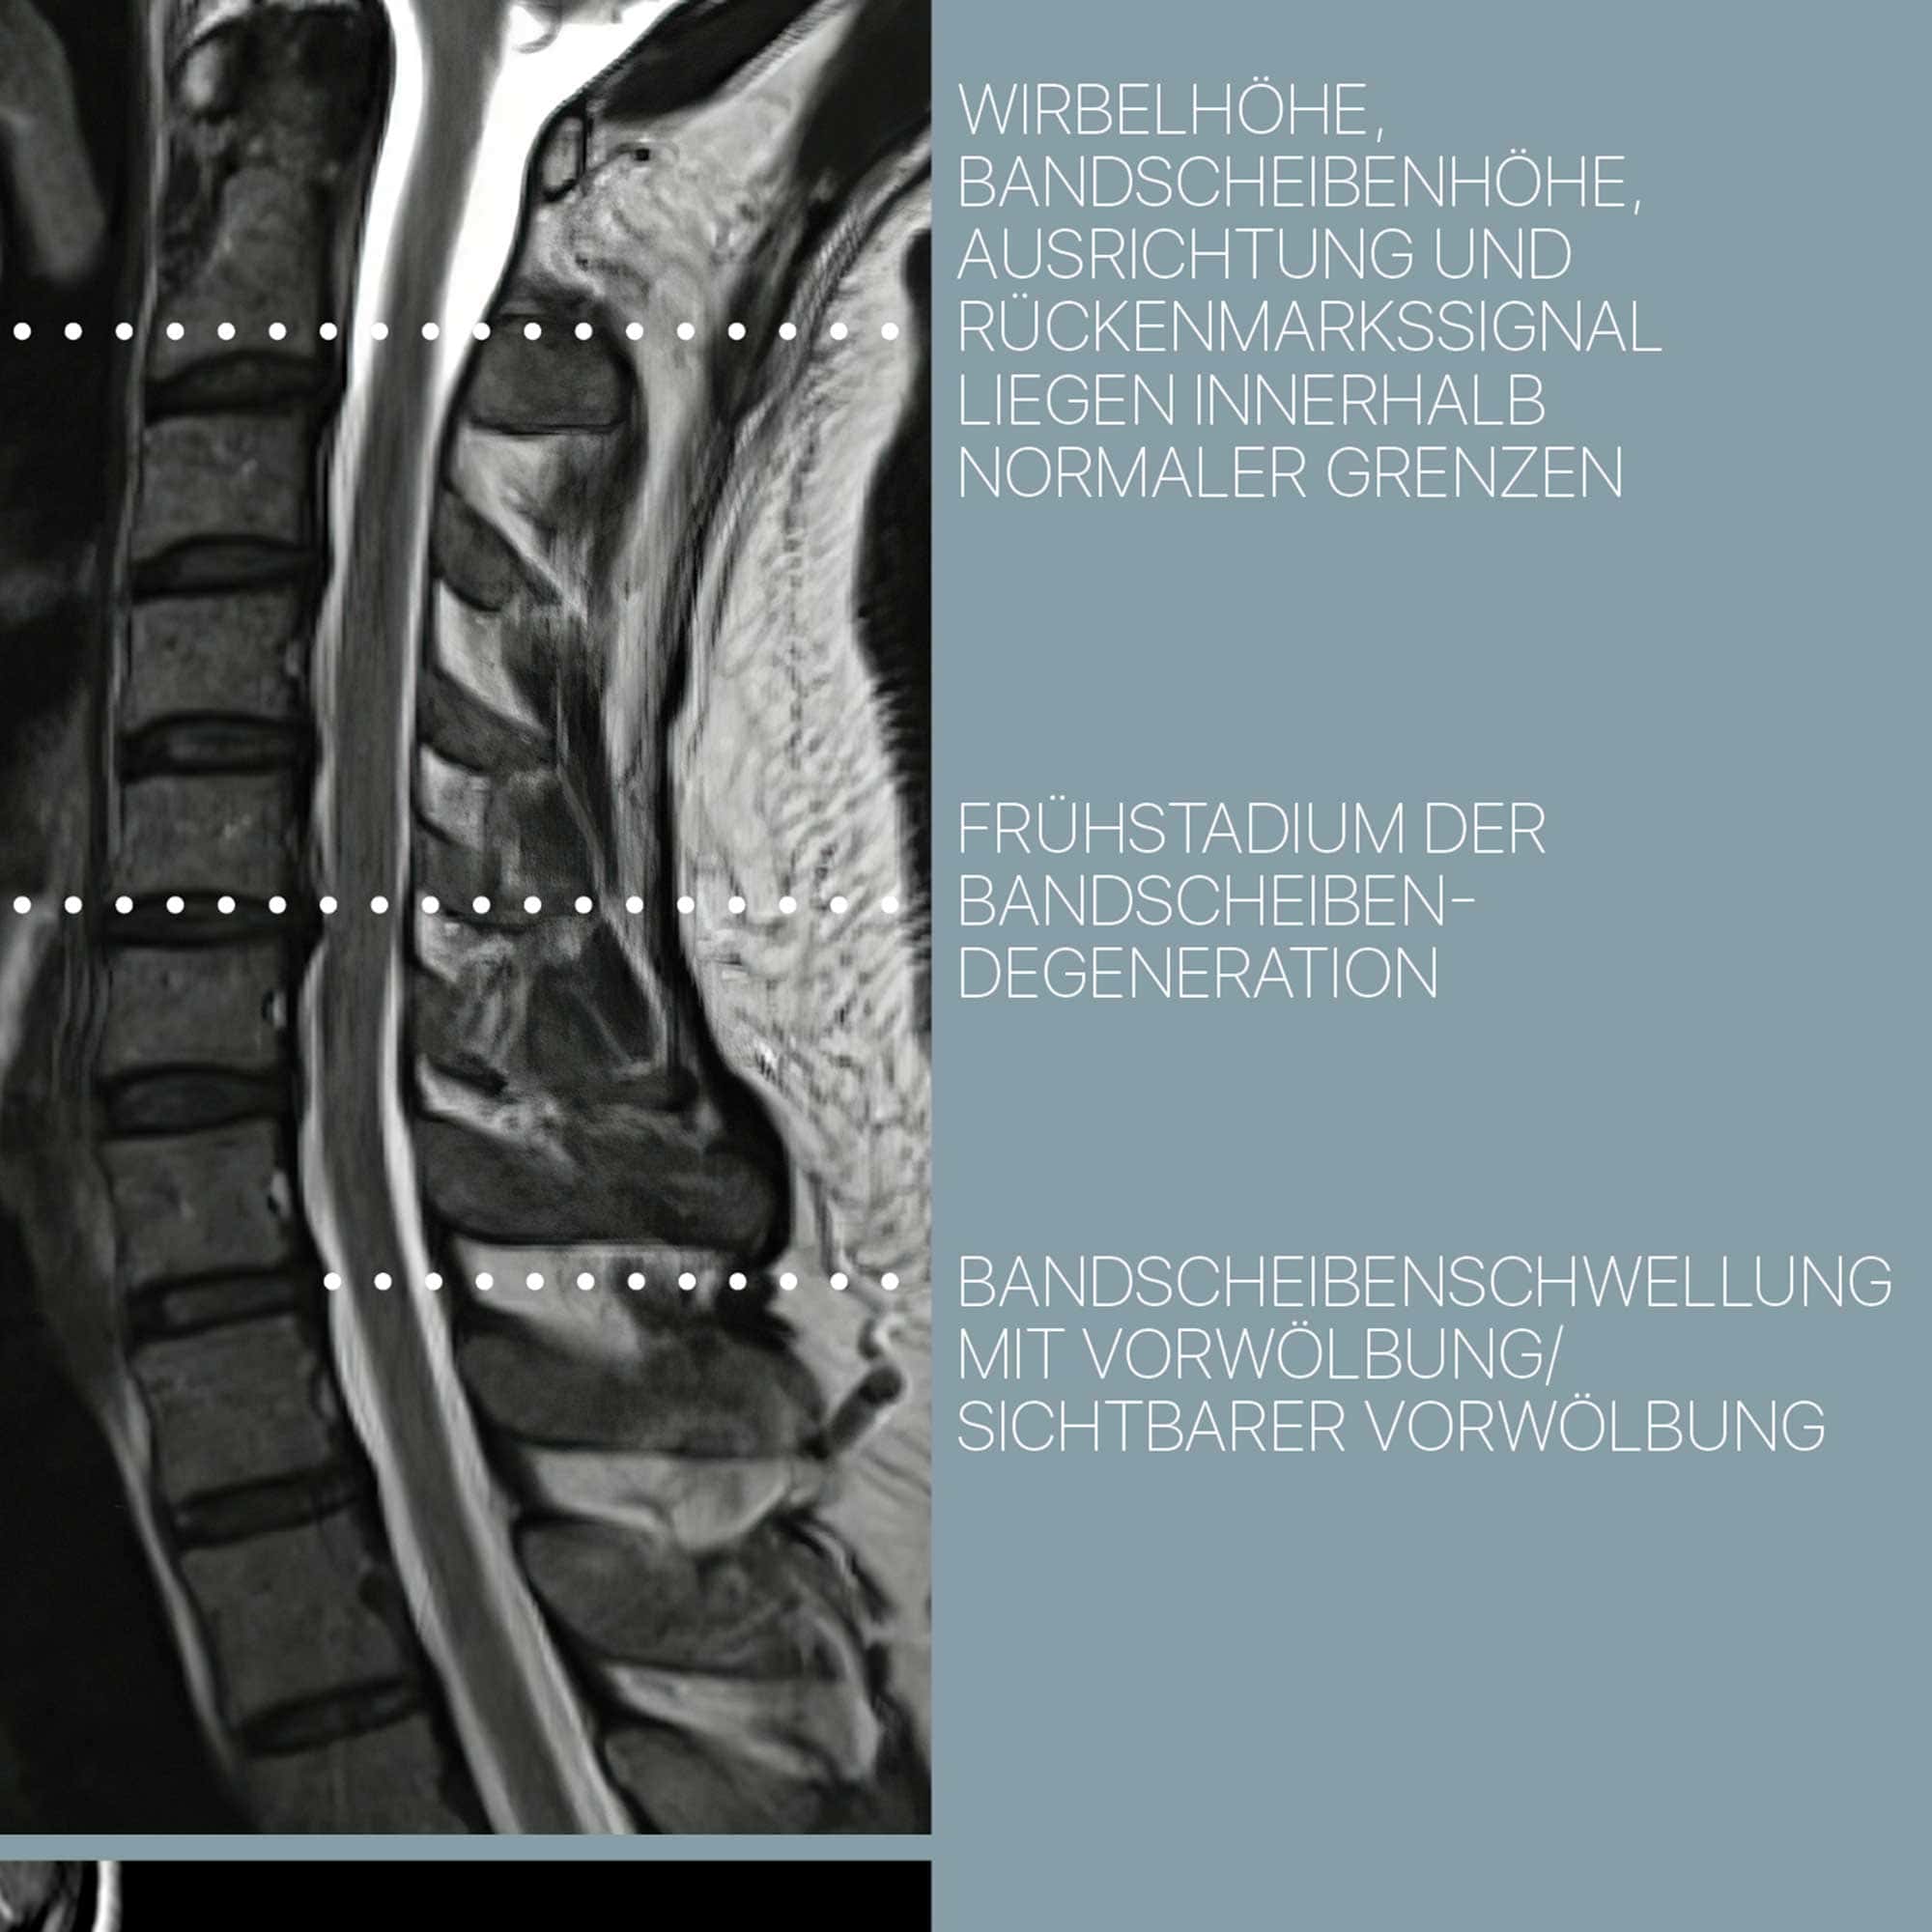

Zervikale Pathologie

fortschreitender Verfall

Wirbelsäule

Degeneration